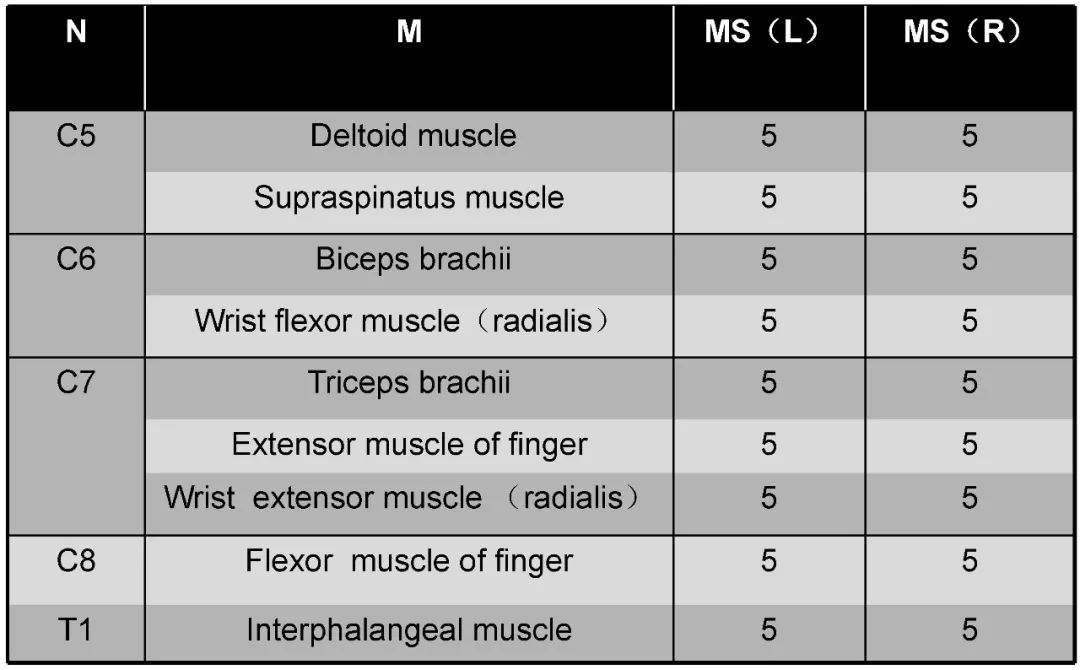

病史:M, 34 y/o

Present History:

Numbness of right lower limb for 2 months, weakness for 1 week

Urination disorder

Past History(-):

Body Weight: 120Kg; BMI: 39.5

术后3个月: